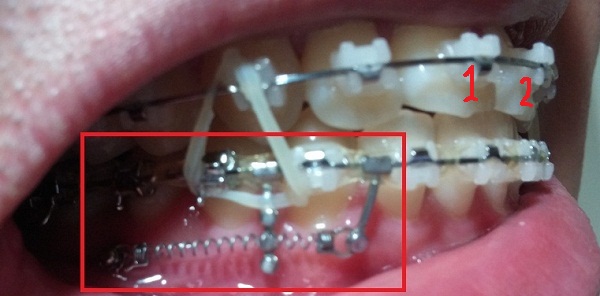

[스프링 정면]

[스프링 옆면]

+스프링사이에 또 다른 쇠기둥 보이시죠?! 저건 스프링이 잇몸에 닿아서 짓눌리지 않게 하기 위해서 해둔 조치랍니다.(제가 눌려서 아프다고 호소했더니 저런 방법으로 해주셨어용^^)

[스프링아래서 본]

-하악 스프링 + 덧대기(잇몸이 눌리지 않게)